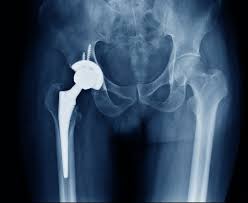

Free hip replacement under the Ayushman Bharat scheme in Amravati provides eligible patients access to advanced orthopedic care without worrying about costs. Severe hip pain from arthritis, avascular necrosis, or trauma can affect daily activities and overall quality of life. Under this government-backed initiative, patients can receive robotic or precision-assisted hip replacement at varunam hospital, guided by the expertise of Dr. Utsav Agrawal, ensuring accurate surgery, faster recovery, and long-term joint function.

Ayushman Bharat offers cashless or fully-funded hip replacement for eligible patients, covering surgery, hospital stay, medications, and diagnostic tests. At varunam hospital, Dr. Utsav Agrawal evaluates each patient’s condition thoroughly and customizes the surgical plan to suit individual anatomy and health needs.

Because robotic or precision-assisted techniques are used, implant placement is highly accurate, reducing complications and promoting better long-term outcomes.